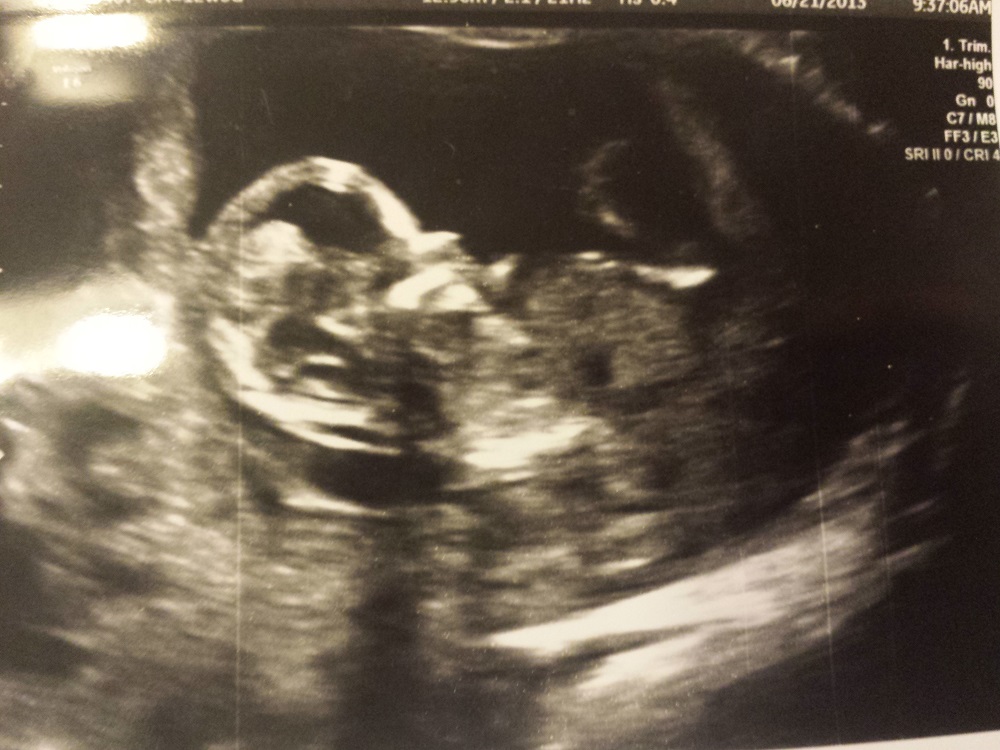

Here is a picture of my 12 week ultrasound. Do you think the skull looks like a girl or boy? We will find out soon! Really appreciate all your guesses! Can't take the waiting anymore and just want to know! Thanks everyone!!

Attachment 14242